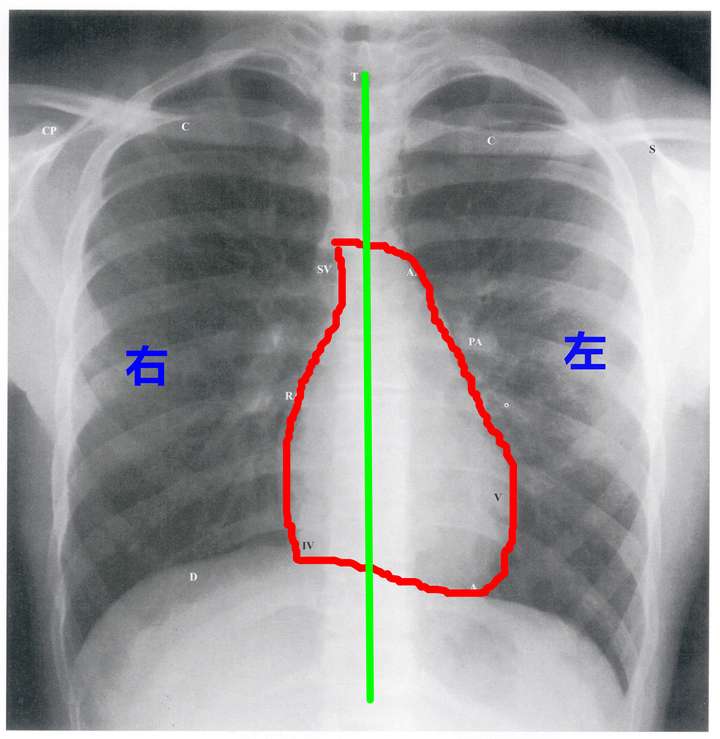

心脏平片分析

此心脏正位片描述正确的是 ( )